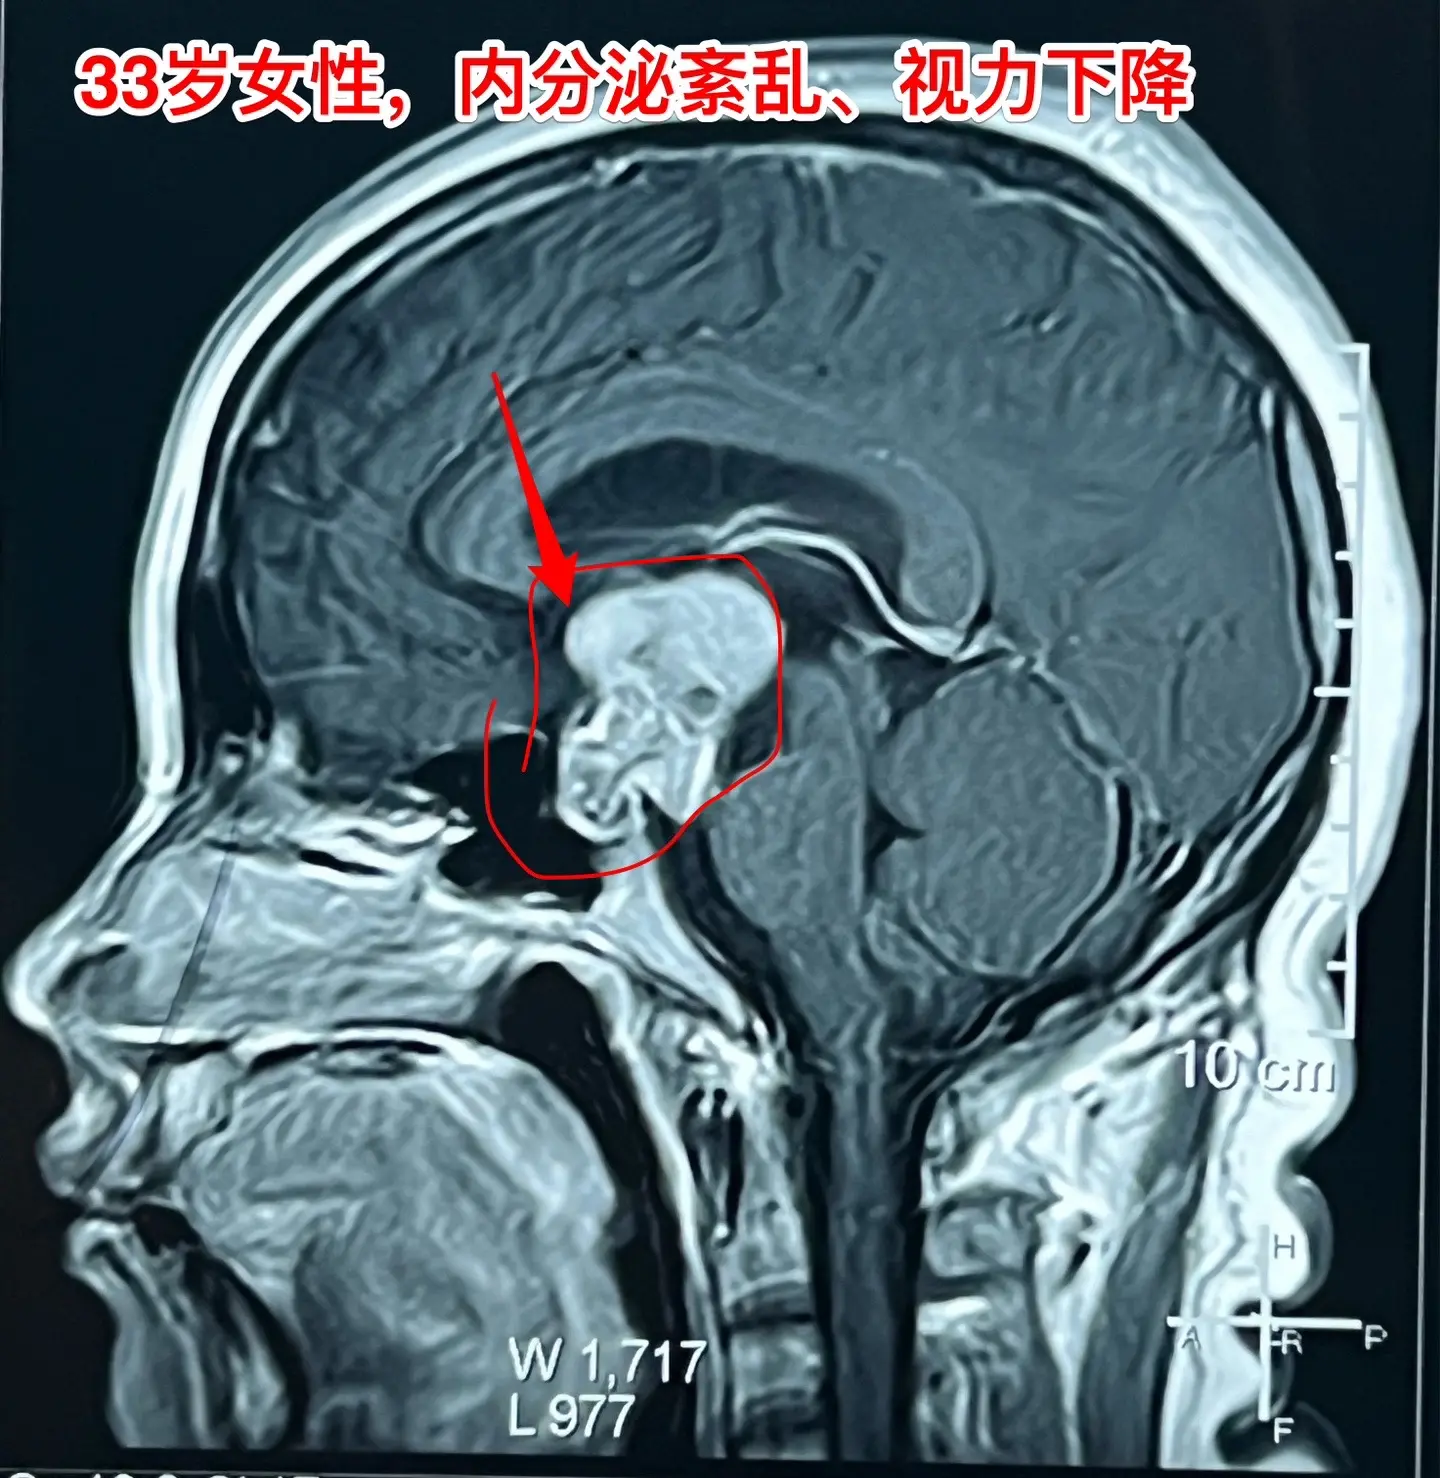

33岁颅咽管瘤患者终于下决心作手术了。洛阳市的女教师,2021年因内分泌紊乱到医院检查,就发现了颅咽管瘤。 由于对手术感到恐惧,再加上工作原因和其他原因,患者一直在观察中,未作手术。 她认识好几个曾经在我这里作过手术的颅咽管瘤病友,每一个成功的手术对她都是一次鼓励! 今年八月份患者和我联系了,说磁共振显示肿瘤在增大,有脑积水了,她也有多睡症状,视力有下降。所以她下定决心要来作手术。 10.28行开颅手术将肿瘤完全切除。肿瘤内有大块钙化,将肿瘤完全切除。手术后患者自述视力有好转。